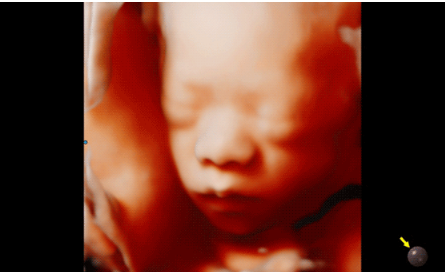

近日三星醫(yī)療推出了一款全新的母嬰超聲系統(tǒng)——Hera i 10。該款產品除了成像能力本身,人性化的座椅設計,探頭擺放位置等也是亮點之一。

Hera i 10繼承并升級了全球首款5D超聲“三星麥迪遜WS80A”的“晶體結構”成像理念,即將CrystalBeam?波束形成技術、CrystalLive?超聲成像引擎、S-Vue Transducer?視覺傳感器集于一身,提供更清晰的圖像。